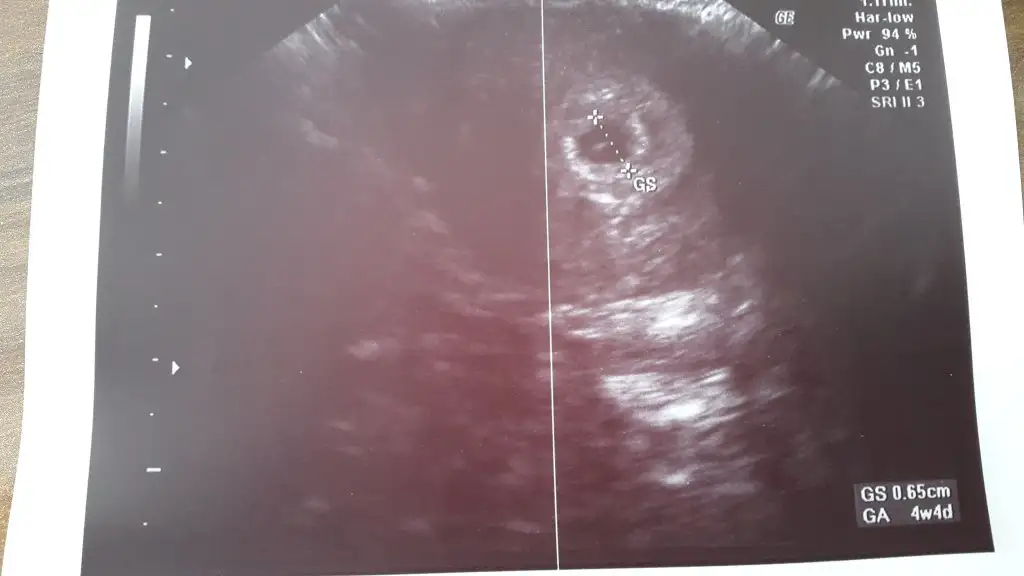

teşekkür ederim, bana idrar testlerimden sanki hcg çok yüksek değilmiş gibi geldi silik çıktı, sonucu yarın alıcam bugün kan verdim. iki günlük bi gecikmem var bakalım değer kaç çıkacakBen gecikmenin 10 günü gittim sonuç buydu karından kese gorunmedi alttan gorundu muayenede 11 günde oldum 4+4 günlük 0.65 cm yazio galiba 6.5 mm olması lazım